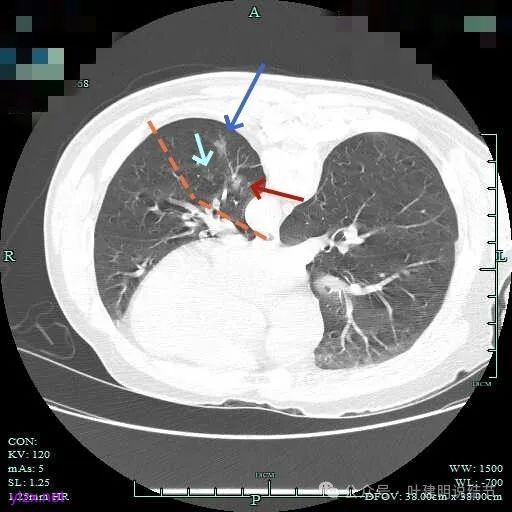

上图蓝色箭头所指的是医用定位胶,天蓝色箭头是次病灶,红色箭头是主病灶,设计的切除线如虚线所示。我们打算进胸后确定定位胶所在平面,因为包括两处病灶均在同一平面上,然后我们游离下肺韧带,将后基底段此部分肺组织向下解剖游离开,直到下肺静脉下缘,并贴着下叶静脉边缘往肺实质深面用切割缝合器切开并闭合肺切缘,按CT上大概距离推算,到越过次病灶深度后转向胸肋面,切除该范围内的肺组织。